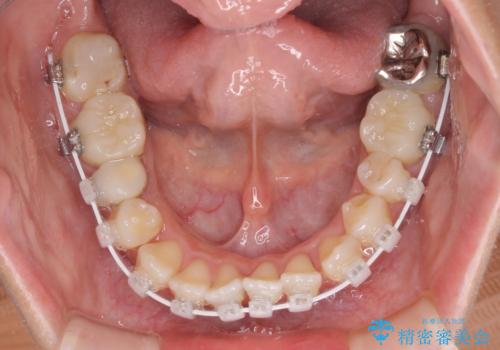

開咬と前突を改善 ワイヤー装置での抜歯矯正

- 矯正装置

- 審美装置

- 口元の突出感と開咬を気にして来院された患者様です。

口元の突出感を改善するため、第一小臼歯を抜歯して口元を引っ込めることとしました。

一般的には上下左右の第一小臼歯4本を抜歯しますが、下顎に対して上顎が前方に位置しているため、まずは上顎小臼歯2本を抜歯し、治療経過を見て下顎小臼歯を抜歯するかどうかを決めていくこととしました。

元々むし歯の処置歯が多く、神経を取り除いている歯が多くありましたが、どうやら右上の前歯と小臼歯は外傷により神経を失った可能性があり、抜歯したスペース前後の歯が全く動かない状態でした。

結果として下顎の小臼歯は抜歯せず、右上の抜歯スペースはむし歯処置を兼ねてオールセラミックブリッジにて補綴治療を行うこととしました。

動かない歯での停滞や、出産と子育てなどにより治療期間は長期化しましたが、整った歯列にて仕上げることができました。